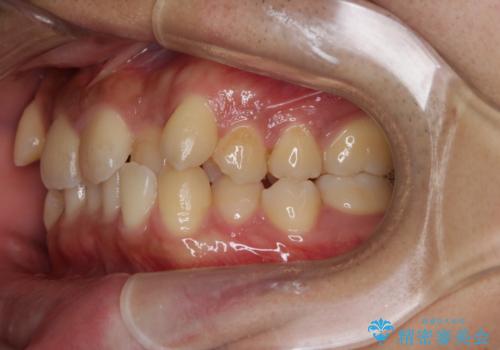

インビザライン単独でここまでできる!!抜歯矯正

- 治療計画

1日20時間以上、正しくインビザラインを使用して頂いたおかげで、ワイヤーに切り替えることなく矯正治療を終了することが出来ました。周囲からも歯並びがすごく綺麗になったと言われたのことで大変ご満足いただけました。